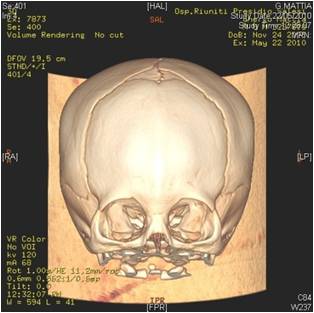

Correzione malformazioni cranio-facciali in età evolutiva ed adulta

Le alterazioni dello sviluppo dello scheletro facciale e delle ossa mascellari , di origina familiare o congenita , si caratterizzano anche con gravi modificazioni dell'occlusione con conseguenti problematiche funzionali ed estetiche. A questo proposito è molto importante intercettare la patologia di accrescimento osseo nell'età prepuberale ed eventualmente eseguire una terapia ortodontica dapprima intercettiva (per provare a risolvere le alterazioni dello sviluppo scheletro facciale) e successivamente di preparazione per l'eventuale intervento chirurgico ortognatico che si prefigge il compito di riposizionare il mascellare superiore e/o la mandibola nel rapporto spaziale anatomicamente corretto, con conseguente riallineamento masticatorio , funzionale ed estetico.

![]() | ![]() | ![]() | ![]() |